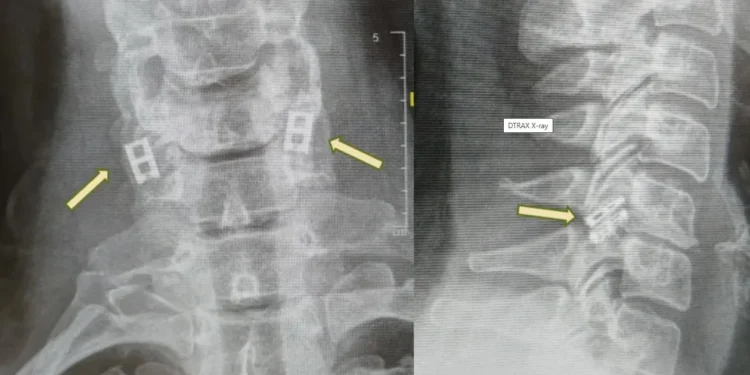

Προς το παρόν, οι τραυματισμοί του νωτιαίου μυελού δεν μπορούν να θεραπευτούν πλήρως, επομένως η θεραπεία επικεντρώνεται στη σταθεροποίηση του ασθενούς, την πρόληψη περαιτέρω προβλημάτων και τη μεγιστοποίηση της λειτουργικότητας. Η επείγουσα φροντίδα περιλαμβάνει συχνά την ακινητοποίηση της σπονδυλικής στήλης, τη μείωση της φλεγμονής και σε ορισμένες περιπτώσεις τη χειρουργική επέμβαση για αποκατάσταση καταγμάτων ή την ανακούφιση από πίεση.

Σε αντίθεση με άλλους ιστούς, οι νευρώνες του νωτιαίου μυελού δεν μπορούν να αναγεννηθούν φυσικά, και με την πάροδο του χρόνου, ο ουλώδης ιστός εμποδίζει τα εναπομείναντα σήματα. Η νέα διαδικασία στοχεύει στην αντικατάσταση του κατεστραμμένου τμήματος με εργαστηριακά καλλιεργημένο νωτιαίο μυελό που συγχωνεύεται με τον υγιή ιστό πάνω και κάτω από το σημείο του τραυματισμού.

Επίσης, συλλέγεται λιπώδης ιστός για τη δημιουργία μιας προσαρμοσμένης υδρογέλης (scaffold), στην οποία τα κύτταρα αυτά αναπτύσσονται σε δομή νωτιαίου μυελού. Αυτός ο τεχνητός ιστός εμφυτεύεται, αντικαθιστώντας τις ουλές και επανασυνδέοντας το νευρικό σύστημα.